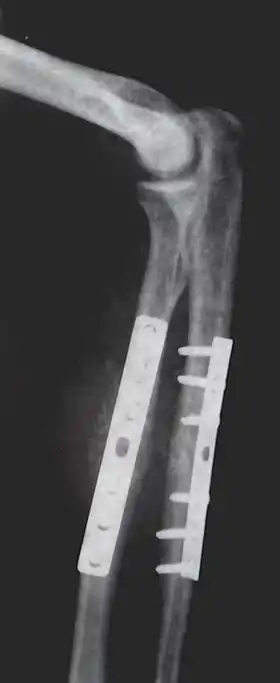

According to applications for board certification from 1999 to 2003, the top 25 most common procedures (in order) performed by orthopedic surgeons are:[22]

- Repair fracture of radius (bone)/ulna

- Repair fracture of the distal part of radius